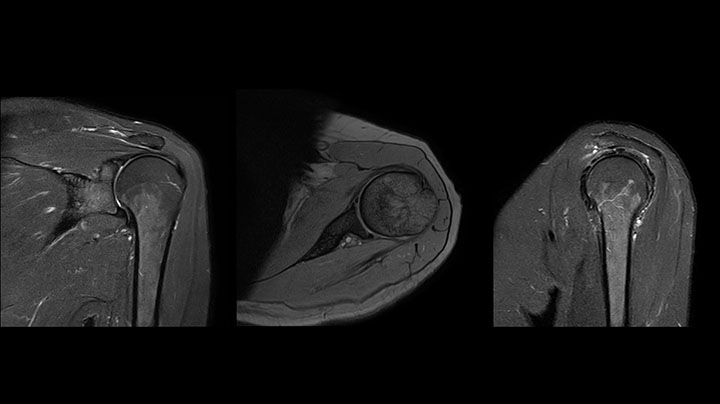

Shoulder MRI with high quality, large coverage

The Prodiva shoulder coil is very flexible and has large coverage, which makes good positioning easier, and that contributes to the superb image quality and high SNR that we get in our shoulder exams.

Scan time 2:55 min, FOV 160 mm,

acq voxels 0.55 x 0.83 x 3.0 mm.

Scan time 4:19 min, FOV 160 mm,

acq voxels 0.55 x 0.80 x 3.0 mm.

Scan time 2:50 min, FOV 160 mm,

acq voxels 0.70 x 0.99 x 3.0 mm.

Shoulder MRI with high quality, T2 SPIR

Shoulder MRI with high quality, mFFE

Shoulder MRI with high quality, STIR TSE